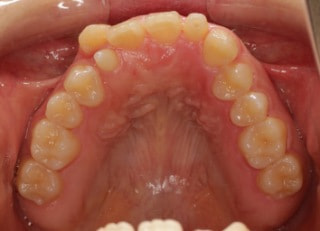

治療後(2年11ヶ月後)

解説:下顎前突上顎劣勢長傾向で、上顎両側2番が矮小歯、右下2番先天欠如症例なので、上下前歯の幅径の比率を調節する必要があるケースです。(ご本人のご都合で治療中に来院できない期間がありました)